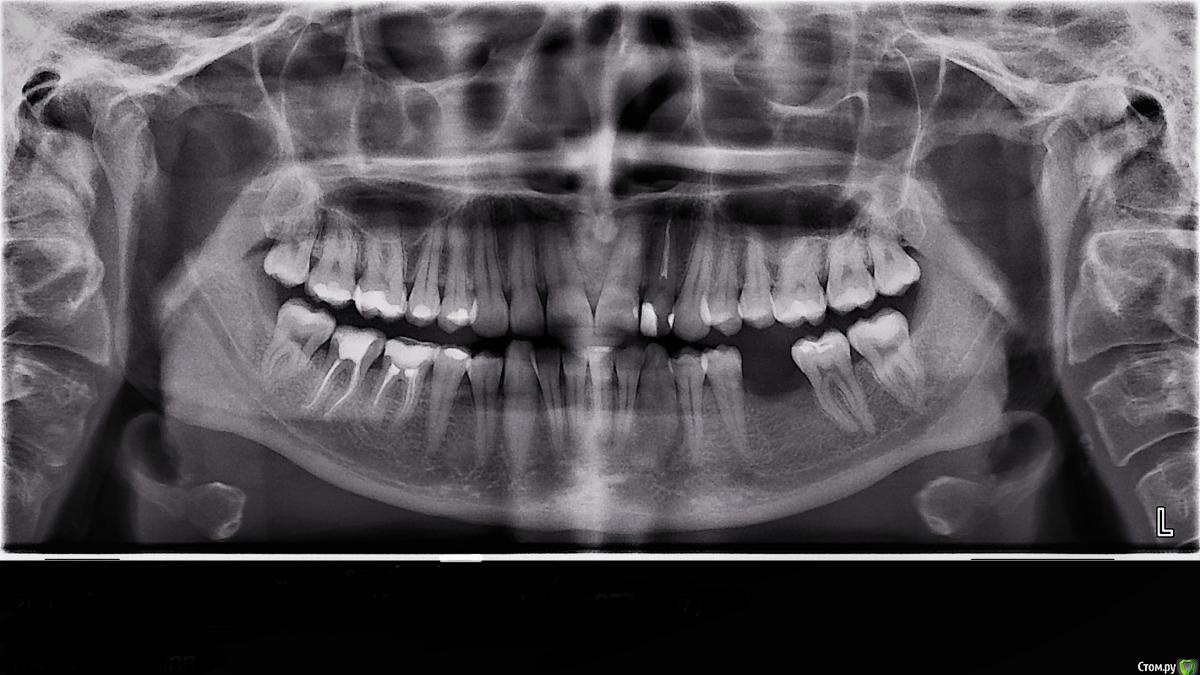

unogirlie Опубликовано 28 апреля, 2017 Поделиться Опубликовано 28 апреля, 2017 Здравствуйте, уважаемые доктора!У меня такой вопрос, есть пролеченная семерка с большой пломбой, кушала сухарик, а край зуба, хрясь...и откололся, причем чуть ниже десны.Врач сказала, чтобы спасти свой зуб нужна коронка, иначе рискую доломать зуб с других сторон. В это я верю. Вопрос в том, что она сказала нужно гребень кости подточить, тк зуб сломался чуть ниже десны, для того чтобы можно было установить коронку. Как вы считаете, действительно это так или можно там пломбой заделать за десну?Также она утверждает, что культевую вкладку ставить не нужно, поскольку у меня крепкий материал уже стоит и этого достаточно, что с вкладкой может также возникнуть проблема с точной установкой коронки. Так ли это?А еще у меня возникла идея, чтобы стянуть зубы на место этой 7, предварительно удалив ее, ну заодно с другой стороны место 6 (был удален несколько лет назад). Подскажите это реально или сомнительно? Спасибо за советы! Ссылка на комментарий

unogirlie Опубликовано 2 мая, 2017 Автор Поделиться Опубликовано 2 мая, 2017 Не сразу увидела, что кто-то написал....Вот как получилось, максимально попробовала увеличить и придать четкости. Что теперь подскажете? Ссылка на комментарий